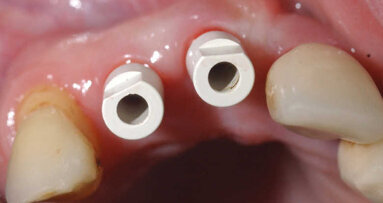

Trois mois plus tard. Second temps du protocole en deux temps. Légère incision crestale, dépose de la vis de couverture et ensuite mise en place de la vis de cicatrisation (Fig. 14).

Dépose de la vis de cicatrisation remplacée par le transfert d’empreinte (Figs. 16 et 17). Prise d’empreinte à l’aide d’un transfert à ciel fermé, silicone en double mélange avec un porte-empreinte du commerce.